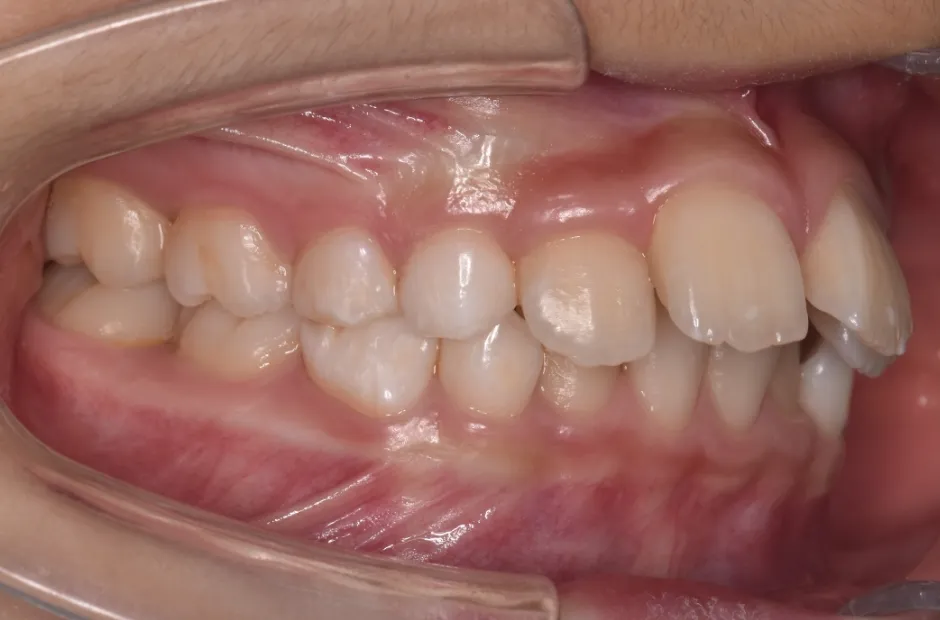

反対咬合

| 診断名・主訴 | 前歯反対咬合 |

|---|---|

| 年齢・性別 | 12歳・男性 |

| 治療期間・回数 | 1年半 18回 |

| 治療に用いた主な装置 | リンガルアーチ(前方誘導弾線) |

| 抜歯部位 | なし |

| 治療費 | 35万円(税抜) |

| リスク・副作用 | 装置による違和感・疼痛・歯肉退縮・歯根吸収・虫歯のリスクなど |

治療前

治療中

治療後